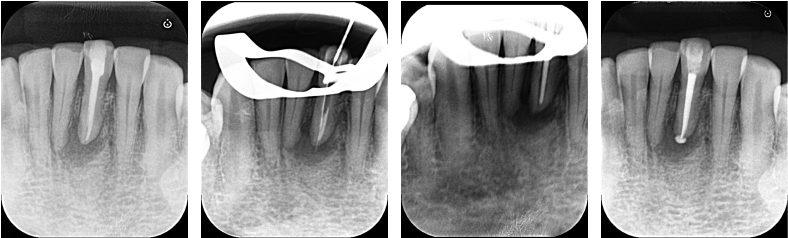

すでに前医にて、根管治療が行われていた状態でした。治療開始前の状態が不目なため正確な判断はできませんが、ラバーダムの使用はされておらず、歯茎の腫れ(フィステル)が残存し疼痛もあるため、再根管治療を行いました。

下顎前歯は歯自体が細いため、歯にストレスを加えないよう最大限留意しながら(クラックを防ぐため)、治療を進めました。

| 根管洗浄 | 次亜塩素酸ナトリウム溶液・EDTA溶液 |

| 根管貼薬 | なし(1回で治療を終えたため) |

| 拡大号数 | 35/04 |

| 根管充填 | バイオセラミックシーラーを用いたHydraulic condensation technique |